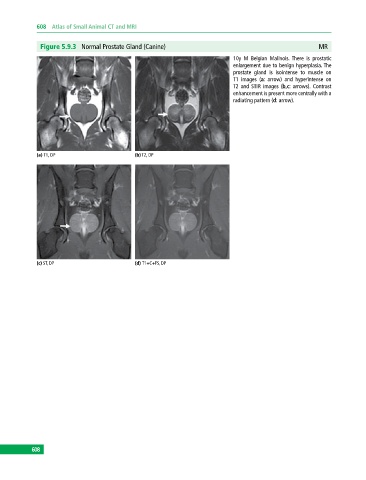

Figure 5.9.3 Normal Prostate Gland (Canine) MR

10y M Belgian Malinois. There is prostatic

enlargement due to benign hyperplasia. The

prostate gland is isointense to muscle on

T1 images (a: arrow) and hyperintense on

T2 and STIR images (b,c: arrows). Contrast

enhancement is present more centrally with a

radiating pattern (d: arrow).

(a) T1, DP (b) T2, DP

(c) ST, DP (d) T1+C+FS, DP